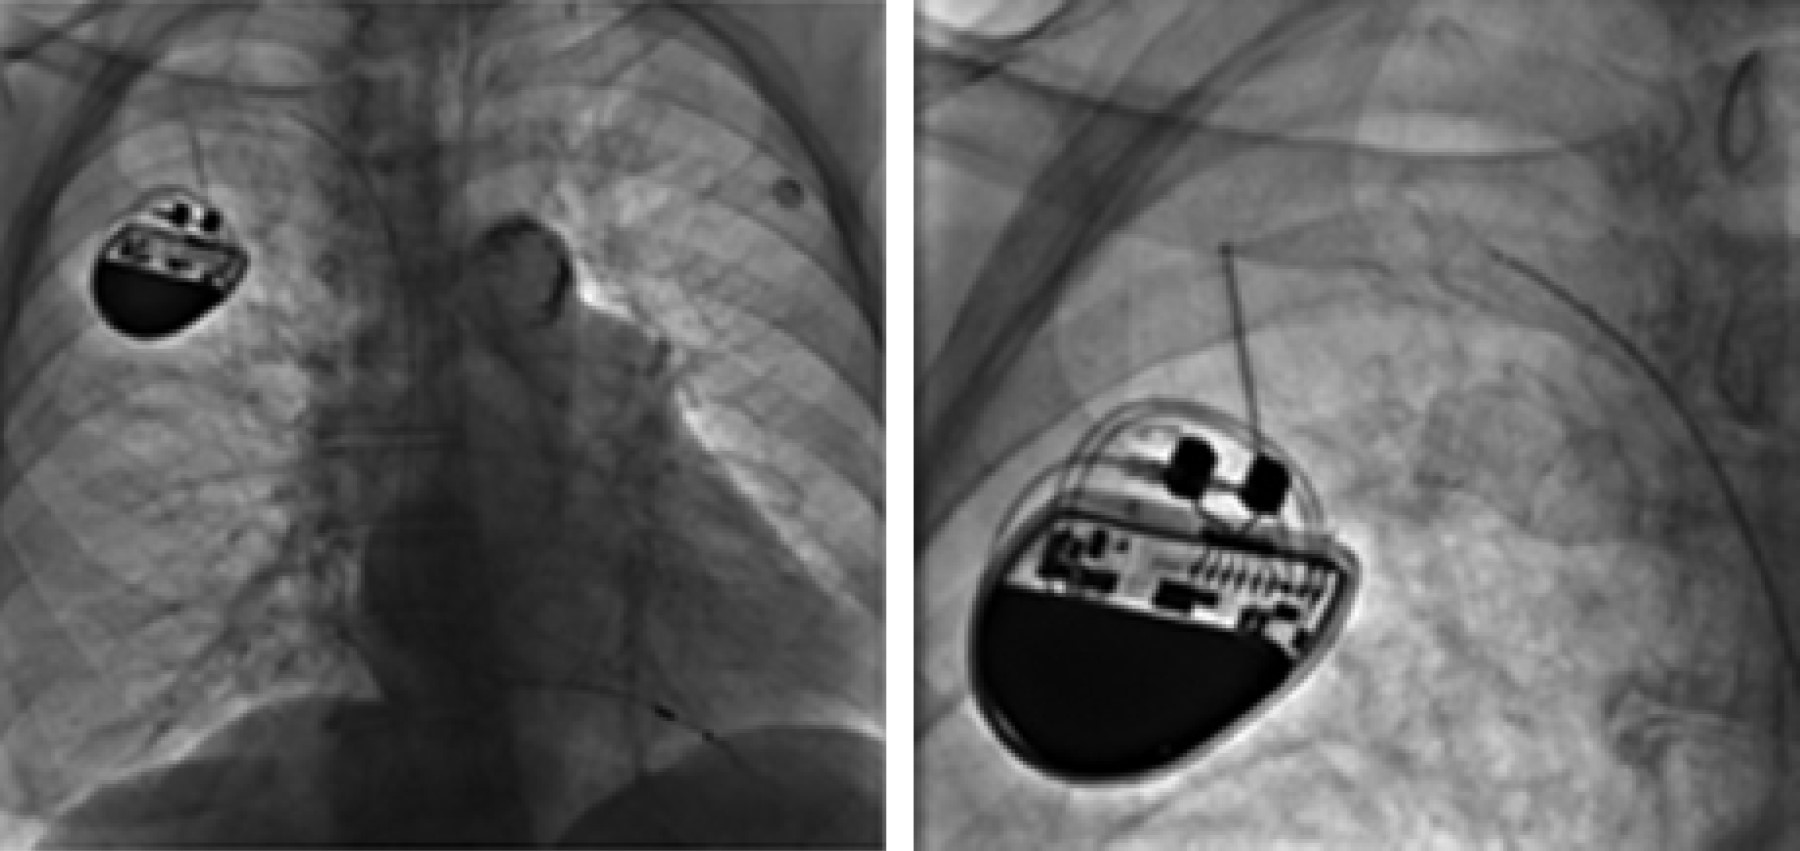

Subclavian crush syndrome. Complete rupture of pacemaker electrode

Figure 1